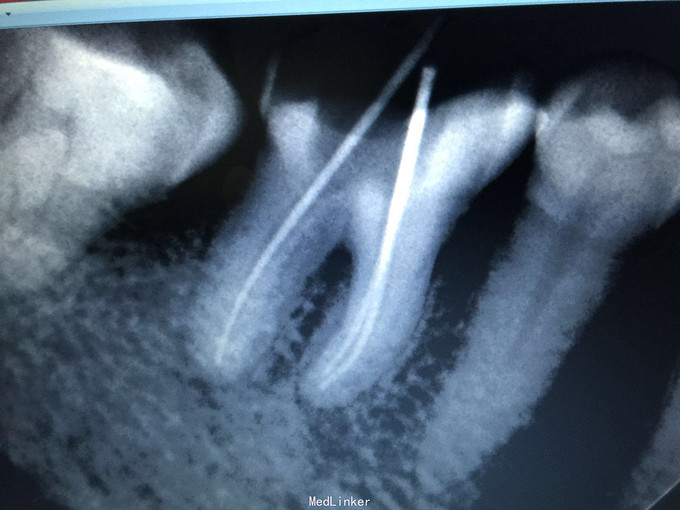

检查:46牙合面重度磨耗近髓,叩诊(+-),松动无,牙龈无明显红肿,冷诊(++)。 X线示:46牙合面缺损近髓腔,根尖无明显低密度影像。

诊断:46急性牙髓炎 治疗:46局麻下开髓揭顶全,慢失活,暂封,肿痛随诊。 二诊:46去暂封及失活剂,根管长度测量,根管预备,冲洗,干燥,根管消毒,根充,适充,锌基,树脂充填,调合,抛光,告医嘱。 建议46冠修复。